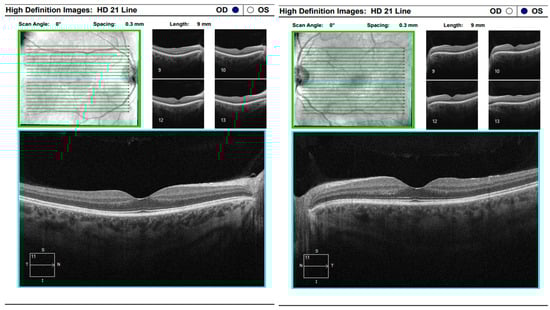

At the scheduled follow-up, although the periocular inflammation had improved, the patient reported markedly blurred vision in the left eye, with BCVA measured at 0.9 and subjective metamorphopsia on the Amsler grid. Biomicroscopy revealed pronounced anisocoria, with the left pupil wider than the right but still reactive to light. Fundoscopic examination was unremarkable in the right eye, while the left eye demonstrated macular edema. Optical coherence tomography (Zeiss Cirrus 5000) confirmed macular edema with isolated cystoid spaces and no evidence of optic disk swelling (Figure 13 and Figure 14). B-scan ultrasonography revealed bilateral scleral thickening, prompting revision of the working diagnosis to probable bilateral scleritis, likely of autoimmune origin. Parabulbar administration of Dexamethasone was performed, resulting in improvement of both subjective symptoms and objective findings.

Approximately six weeks later, the patient presented with complaints of transient, painless visual loss. Examination revealed visual acuity of 1.0 in both eyes, however red color perception was impaired in the right eye. Biomicroscopy of the anterior segment was unremarkable in both eyes. Fundoscopic evaluation demonstrated blurred and indistinct optic disk margins in the right eye, consistent with papilledema, while the left eye appeared normal (Figure 15). Given these findings, the patient was admitted urgently with a working diagnosis of optic neuritis, and intravenous pulse corticosteroid therapy was initiated.

Figure 13. Analysis protocol “HD 21 Line” of the right and left eye.

Figure 14. Analysis protocol “Optis Disk Cube 200 × 200” on the right and left eye.

Figure 15. Analysis protocol “Optis Disk Cube 200 × 200” on the right and left eye.